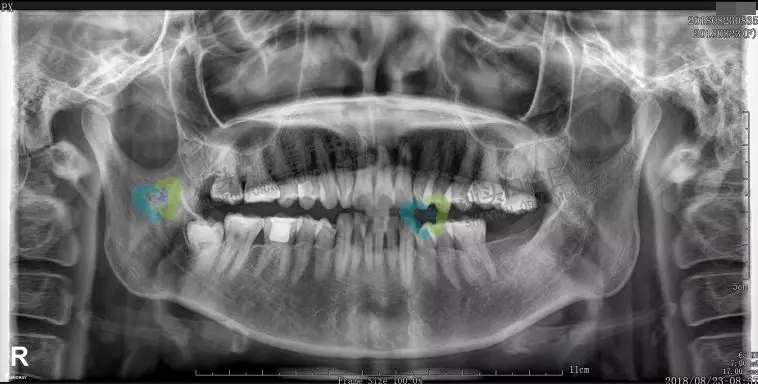

口腔全景牙片,是通過一次拍攝將全口牙齒和頜骨的影像清晰的顯示在一張X光片上,可以清晰、完整的顯示上頜骨、下頜骨全貌,上下頜牙列情況,牙槽骨情況,能夠清晰顯示上頜竇腔、竇壁、竇底情況以及顳頜關(guān)節(jié)情況,并對(duì)頜骨周圍疾病的診斷提供準(zhǔn)確有效的幫助。